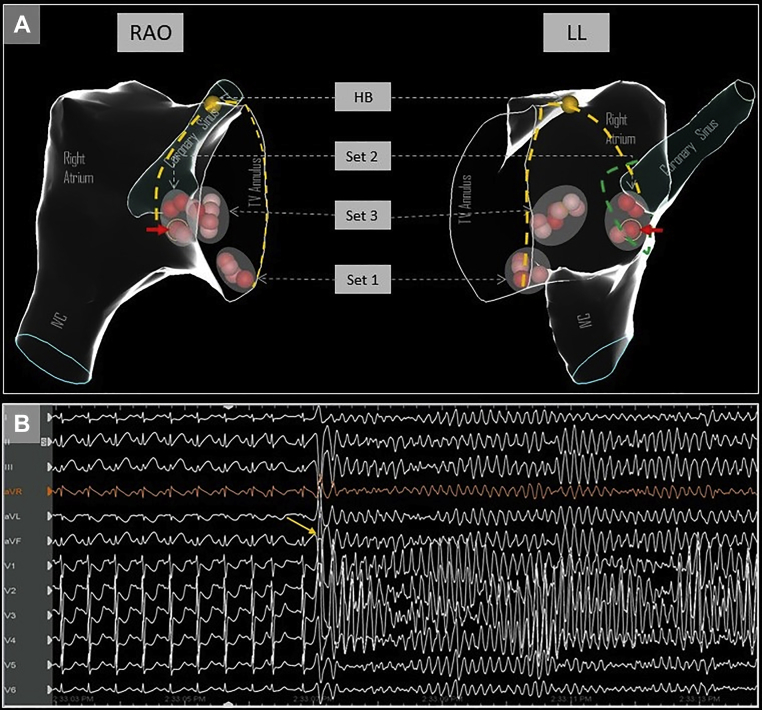

The CSO was defined by a combination of electroanatomic mapping using the ablation catheter, fluoroscopy, near-field atrial electrogram (usually similar or larger amplitude than ventricular signal) and 10 Ω rises in impedance from the baseline. Ablation was performed with a nonirrigated catheter (50 watts, temperature limit 60°C), and this was used for all ablation lesions that are depicted in Figure 1A. Individual lesion characteristics are outlined in Table 1. Breath-hold was utilized for all ablation lesions to avoid respirophasic catheter movement, and there were no appreciable steam pops with any of the lesions. Initial ablation lesions were delivered in the inferior portion of the triangle of Koch (set 1 in Figure 1A) without inducing junctional ectopy. After a few short test lesions in the region indicated by set 3, additional lesions were delivered in an area that was felt to be anterior to the CSO (set 2 in Figure 1A); these lesions were also prematurely terminated owing to impedance rises (>10 Ω) or lack of junctional beats seen. Final ablation lesions were again delivered more anterior to the CSO area, which resulted in junctional beats (set 3 in Figure 1A) and the endpoint of noninducibility.

Figure 1.

A: Electroanatomic views in right anterior oblique (RAO) and left lateral (LL) orientation showing the different sets of ablation lesions delivered, and relationship to His bundle area. The red solid arrow indicates the culprit lesion following which ST changes were seen. The yellow dashed lines mark the anterior and posterior borders of the triangle of Koch. The green dotted line shows the possible outline of a funnel-shaped coronary sinus ostium, indicating that the ablation lesion could have been within the ostium. HB = His bundle; IVC = inferior vena cava; TV = tricuspid valve. B: Ventricular fibrillation induced by R-on-T premature ventricular contraction (yellow arrow).

Following this, isoproterenol (10 mcg intravenous bolus) was administered, and testing was repeated with abolition of AH jump. Approximately 4 minutes after isoproterenol administration, the patient developed spontaneous VF from an R-on-T premature ventricular contraction (Figure 1B), requiring defibrillation. This rather unusual finding raised suspicion for CA injury, and review of the surface 12-lead electrocardiogram (EGC) at a 25 mm/s sweep speed showed precordial ST-segment depression (Figure 2A, red arrows) with subtle elevation in the inferior leads (Figure 2A, red arrowheads) after 1 of the ablation lesions (Figure 1A, red arrows). The 12-lead ECG during the entire ablation lesion as well as a plot of biophysical parameters during this ablation lesion are shown in Supplemental Figure S1; there was a gradual increase in impedance of >10 Ω, after which ablation was terminated. These subtle ECG changes post ablation were not evident on 200 mm/s sweep speed that is used during EP study and ablation (Figure 2B and C). Emergent coronary angiography was performed with a JR4 guide catheter, which revealed complete occlusion of the right posterolateral branch of the right CA (Figure 3A and D). Intracoronary nitroglycerin and verapamil were administered through the guide catheter, without improvement in appearance or flow. Percutaneous transluminal coronary angioplasty (PTCA) was performed, which resulted in flow restoration. However, there was residual stenosis followed by complete reocclusion resulting in ST changes and another episode of VF requiring defibrillation. Repeat PTCA was attempted, with administration of additional vasodilators; however, the vessel continued to occlude, suggesting extrinsic compression from myocardial edema or direct thermal injury to the artery. Coronary stenting was performed with a Xience Alpine 2.25/15 drug eluting stent (Abbott Laboratories), with successful resolution of ST changes and TIMI 3 flow with good myocardial blush (Figure 3B and E).